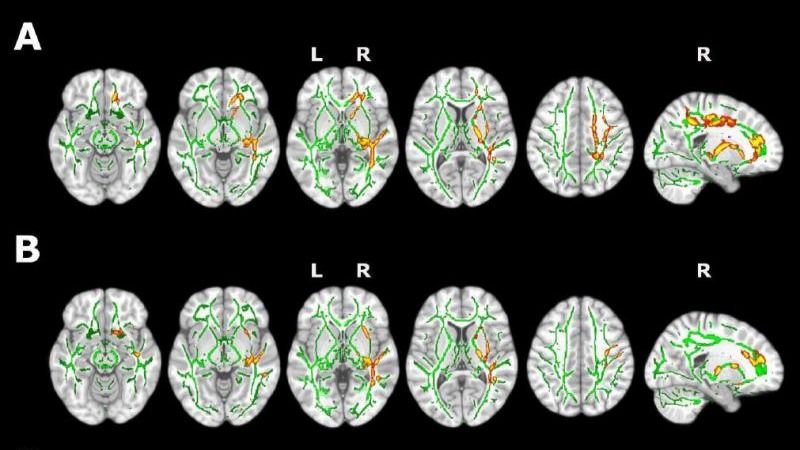

Además, el estudio demostró, gracias a imágenes de resonancia magnética, que los participantes con insomnio presentan un menor volumen en algunas regiones cerebrales. Entre ellas se encuentran el precúneo o el córtex cingulado posterior, que se encuentran afectadas en etapas tempranas de la enfermedad de Alzheimer. Los resultados apoyan las investigaciones que relacionan la presencia de insomnio con una elevada vulnerabilidad a esta patología.

El presente estudio encontró, además, cambios en la sustancia blanca cerebral mediante técnicas de resonancia magnética por difusión. A este respecto, el primer autor del estudio, Oriol Grau, destacó que “estos hallazgos sugieren la presencia de procesos de inflamación cerebral que podrían tener un papel clave en la asociación entre la calidad del sueño y el alzhéimer”.